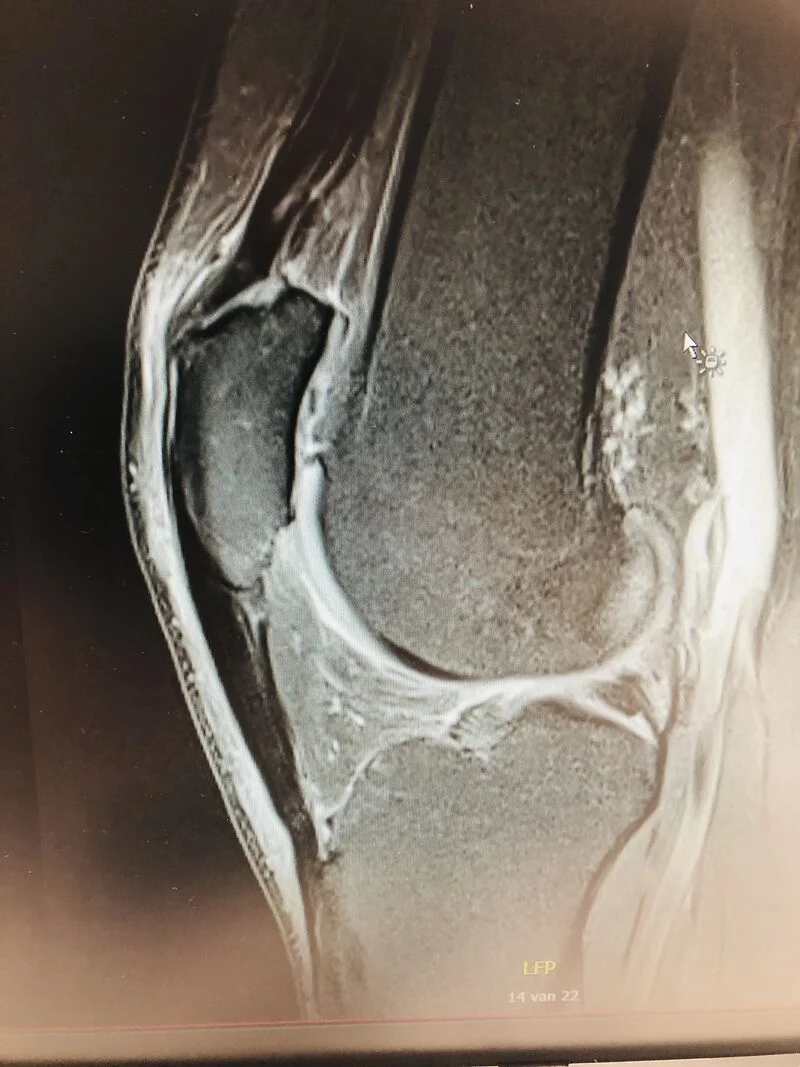

This patient (admittedly n=1) had no positive effect of hyaluronic acid injections for patellofemoral OA.

Patient had a hematological contraindication for PRP treatment. After 3 hydrolysed collagen peptide injections, the pain improved by 70% now 3 months out from the last injection.

These collagen injections in my practice offer a valuable alternative (biologic?) therapy for patients in whom platelet-rich plasma (PRP) is contraindicated and hyaluronic acid injections failed to provide enough improvement in symptoms.